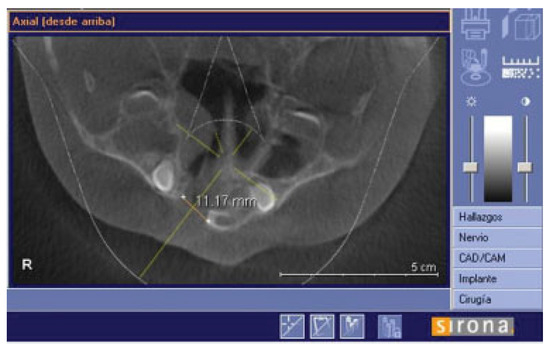

There were no intraoperative or postoperative complications. The fissure length in the upper edge when measured with a rule tool in the CBCT with Sirona Galileos software range from 5.76 to 16.93 mm (mean, 11.18 mm) (►Figure 4). All patients in the DBM group underwent a second CBCT assessment after 6 months of the surgical procedure. In the axial, coronal, and sagittal views and the three-dimensional reconstruction, there was no bone formation in none of the patients. The highest grayscale value in the area of the cleft was registered (►Figure 5), finding gray values between 1,148 and 1,496 (mean, 1,278.15). In our patients, the gray values corresponding to the bone adjacent to the cleft were higher than 1,504. During the follow-up performed 15 to 33 months postoperatively (mean, 28.2 months), occlusal and periapical X-ray were performed and analyzed by applying the Enemark scale; satisfying bone formation of 75% was observed only in just one patient. Four patients were reoperated with conventional surgery, using iliac crest grafts, because they need orthognathic surgery with Le Fort I osteotomy. At the time of reoperation, no bone formation was observed, although a crystallized material was seen in the pocket (►Figure 6) and was removed.

Figure 4.

Axial slide to show how the fissure was measured in the upper edge.